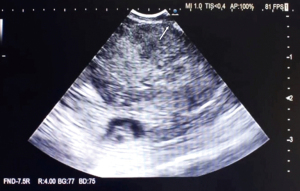

Step 2: the puncture (the first puncture will guide the rest of the process)

Based on our experience, we recommend that this procedure be performed by two operators. While a high skill bronchoscopist in EBUS-TBNA may be able to perform the technique after mastering the learning curve, we can ensure that having two operators makes the process easier, quicker, and safer. Sedation was performed with midazolam (0.07 mg·kg−1) and fentanyl citrate (0.5–2 µg·kg−1), starting with boluses of 1–3 mg of midazolam and 0.1 µg of fentanyl citrate. Sedation was maintained with intermittent boluses of 1.2 mg midazolam and 0.1 µg fentanyl citrate according to the clinical judgment of the pulmonologist. When viewing the ultrasound image, it is important to always use the Doppler mode to avoid any vessels (Figure 2A), carefully choose the location with the thinnest mucosa and lymph node capsule (Figure 2B), and steer clear of any cartilages before performing the TBNA (Figure 2C). The use of Doppler is essential in this procedure. Here we show a significant distance between the TBNA entry point and the lymph node capsule. This distance is due to the enlarged mucosa and cartilage, which should be avoided during the procedure (Figure 3A,3B).